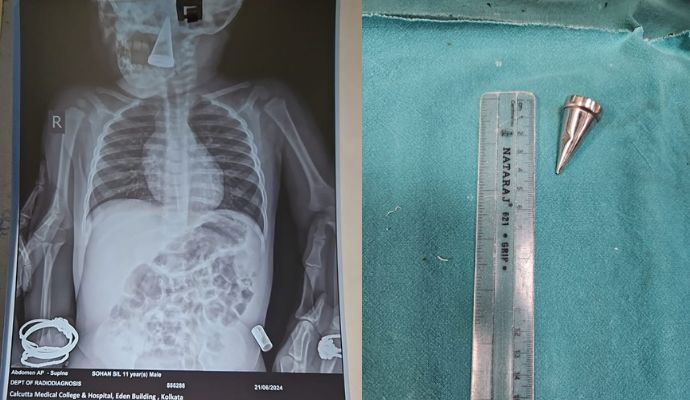

শ্বাসনালীর মধ্যে ঢুকে গিয়েছিল মরচে ধরা ধাতব পিন, মরণাপন্ন বালকের প্রাণ বাঁচাল কলকাতা মেডিক্যাল কলেজ ...

গলা থেকে ধাতব পাইপিং ব্যাগ বার করে শিশুকে বাঁচাল মেডিক্যাল কলেজ ...